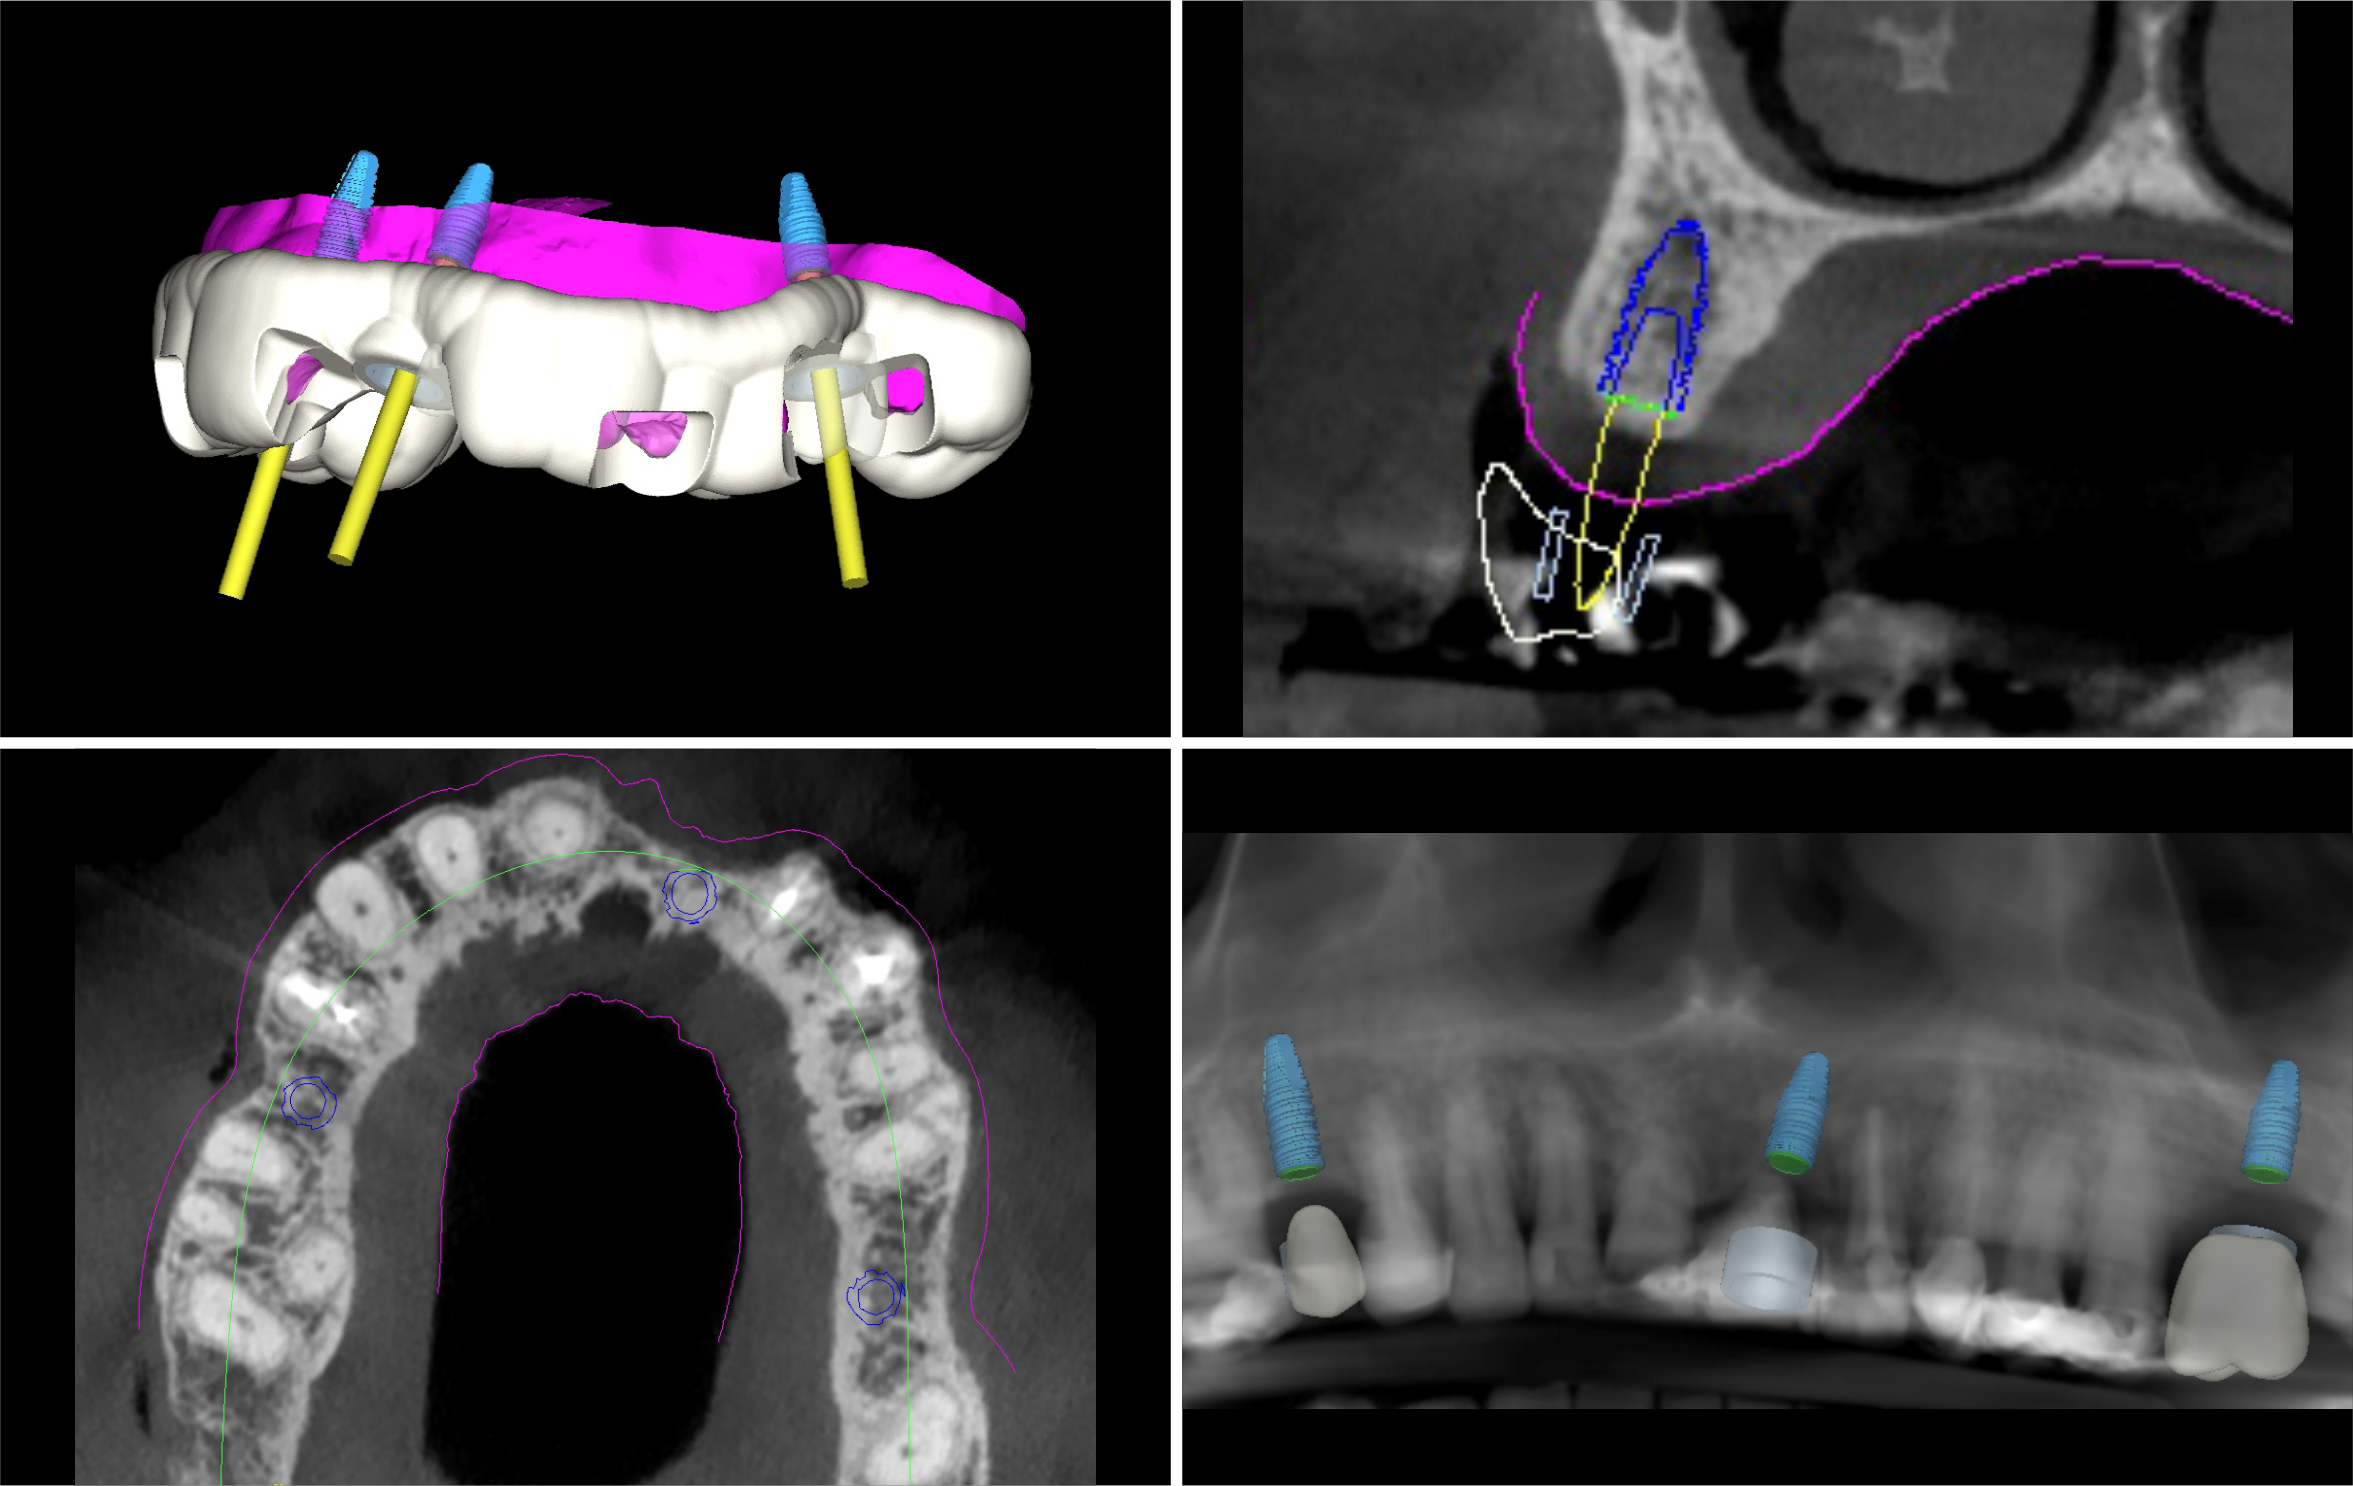

É o procedimento da realização de implante(s) de maneira guiada, com total segurança, uma cirurgia com possibilidade de não haver cortes, reduzido sangramento e pós-operatório rápido e na grande maioria das vezes totalmente indolor. Para obter o guia é necessário fazer tomografia e escaneamento da arcada dentária. Com esses exames e um software de planejamento será feito o planejamento em 3D dos implantes e gerado uma guia de implantes, a qual será posicionado em boca para direcionar a correta perfuração e instalação dos implantes. A precisão do posicionamento dos implantes com o uso do guia, permite, além dos benefícios cirúrgicos, que o(s) dente(s) da prótese já possam ser confeccionados previamente, e já estarem prontos para serem instalados no dia da cirurgia.